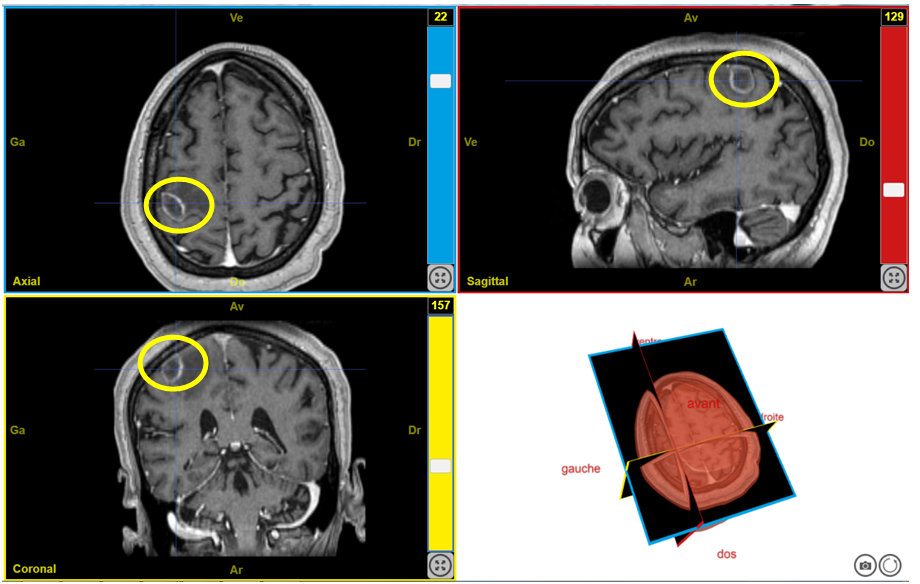

Deficit moteur T1Bravo